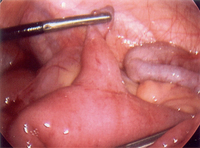

Intraoperative photo of Meckel's diverticulum

From the collection of Dr Kuojen Tsao; used with permission